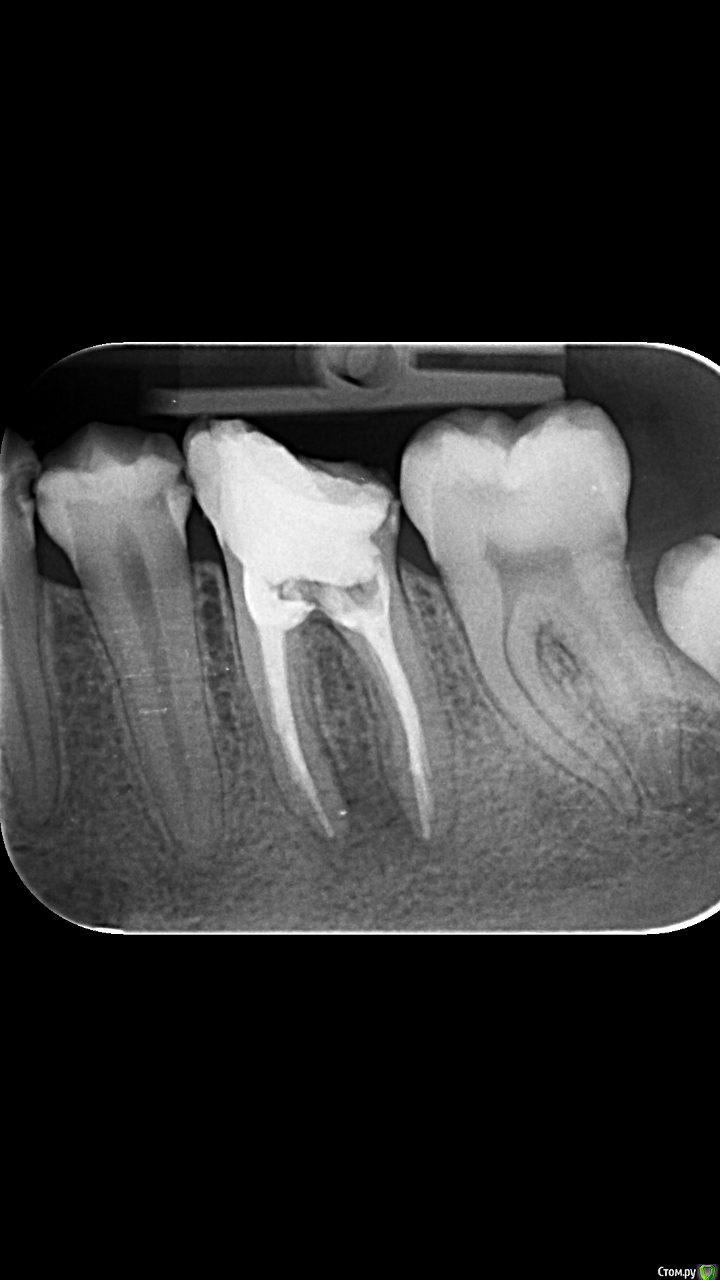

Studentic Опубликовано 17 ноября, 2019 Поделиться Опубликовано 17 ноября, 2019 Здравствуйте! Подскажите как лучше восстановить 3.6 зуб после эндодонтии? Вкладка + коронка? Ссылка на комментарий

Studentic Опубликовано 17 ноября, 2019 Автор Поделиться Опубликовано 17 ноября, 2019 Пациент сохранить его очень хочет, да и мне интересно что получится из этого. Весь кариес удалил, дно полости зуба твердое, веду на кальции, симптомов нету. Было бы хорошо его спасти Ссылка на комментарий

Бардо Опубликовано 17 ноября, 2019 Поделиться Опубликовано 17 ноября, 2019 Прицервикального дентина, видимо, осталось все же не много (вам виднее), поэтому если вы ещё не успели набить шишек в конфликтах с пациентами из-за неудач в лечении, то это отличный шанс. Опять же, если пациент ваш родственник, коллега или просто хороший парень, я всегда сам лично за вытягивание всякого треша 2 Ссылка на комментарий

Kolchanov Опубликовано 17 ноября, 2019 Поделиться Опубликовано 17 ноября, 2019 Для введения вкладки и минимализации цементного зазора, возможно, придется убить оставшееся. Я бы делал адгезивно. 1 Ссылка на комментарий

krokomot Опубликовано 18 ноября, 2019 Поделиться Опубликовано 18 ноября, 2019 По снимку зуб весьма печален, покажите финальный снимок с эндо, тканей очень мало, штифт добьет зуб я бы делал только композитом билдап, если хотите экспериментировать, учтите, что в случае удачи пациент скажет "хорошо, что не дал удалить", а в случае неудачи будет криворукий доктор, либо доктор хапнул с безнадежного зуба. 2 Ссылка на комментарий